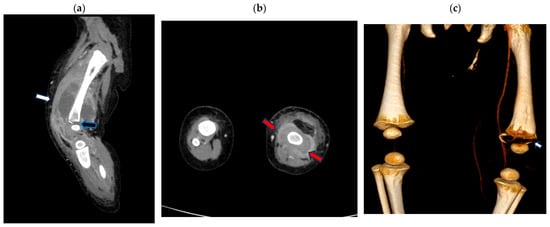

| F/0.28 | 2005 | DTAP + HEPB + IPV/LL (PEDIARIX); HIB/RL (ACTHIB); PNEUMO/RL (PREVNAR) | 9 | Fever, irritability, abdominal pain; bilateral otitis media; swelling of left upper leg; osteomyelitis of left femur and fifth-digit abscess. Chronic osteomyelitis of the left femur | Increased density of soft tissue due to edema, the stranding of subcutaneous tissue, and left quadriceps musculature; “linear metaphyseal lucency of distal femur” (XR). Subperiosteal abscess in the left femur, antero-lateral in the proximal region and circumferential in the distal portion (CT). Pathological fracture of the proximal portion of the femoral metaphysis (XR). | MRSA and coagulase-positive Staphylococcus (culture of wound samples from leg and finger) | IV clindamycin and IV vancomycin and rifampicin. “Ultrasound guided incision and extensive drainage of subperiosteal abscess of left femur; drainage of fifth digit abscess; Surgery of a large subperiosteal abscess (recurrence) and a small intramuscular abscess” | Yes |